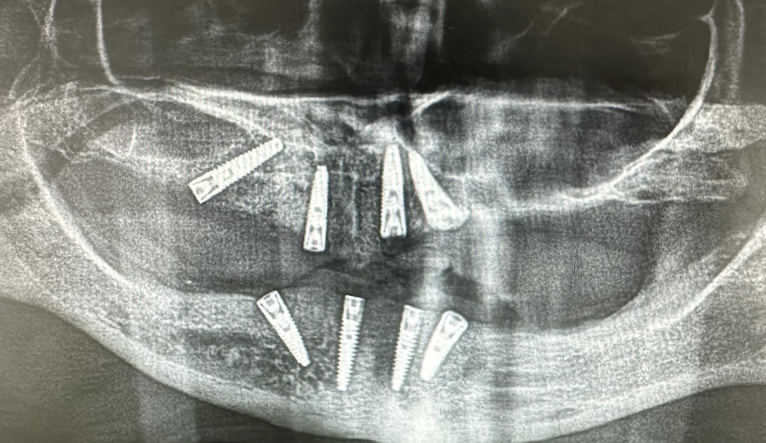

Foto: Dental Centar Jelić

Dentalni implantati ugrađuju se u čeljust i njihovo učvršćivanje traje 3 do 4 mjeseca – kontrolira se rendgen slikom.

Kontrola rendgen slikom. Foto: Dental Centar Jelić